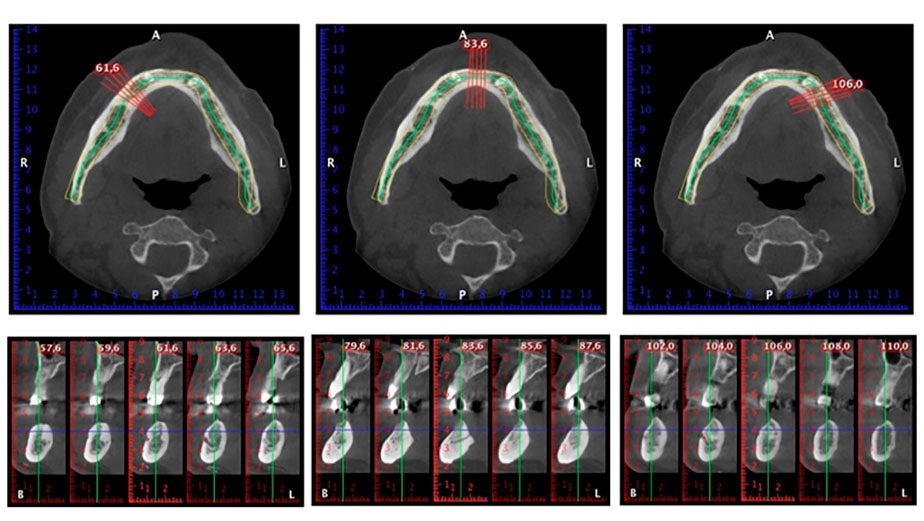

Un CT Scan à faisceaux coniques tridimensionnel (CBCT, Planmeca) a été réalisé au préalable afin de réduire les risques. Il a révélé une qualité et une quantité d'os disponible suffisante pour l'intervention chirurgicale et la restauration immédiate par la méthode All-on-four. En suivant le protocole de ce concept, les implants sont insérés au niveau de 35, 32, 42 et 45 en inclinant les implants distaux jusqu'à 45°, le profil d'émergence se déplace ainsi vers l'arrière et produit un polygone de stabilisation plus large (Fig. 3).